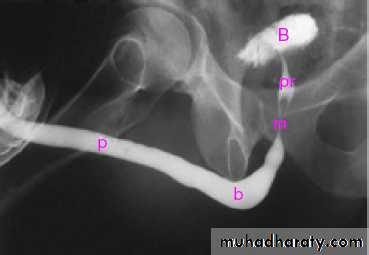

male &female reproductive tractsmammogram

genital tract and mammogram